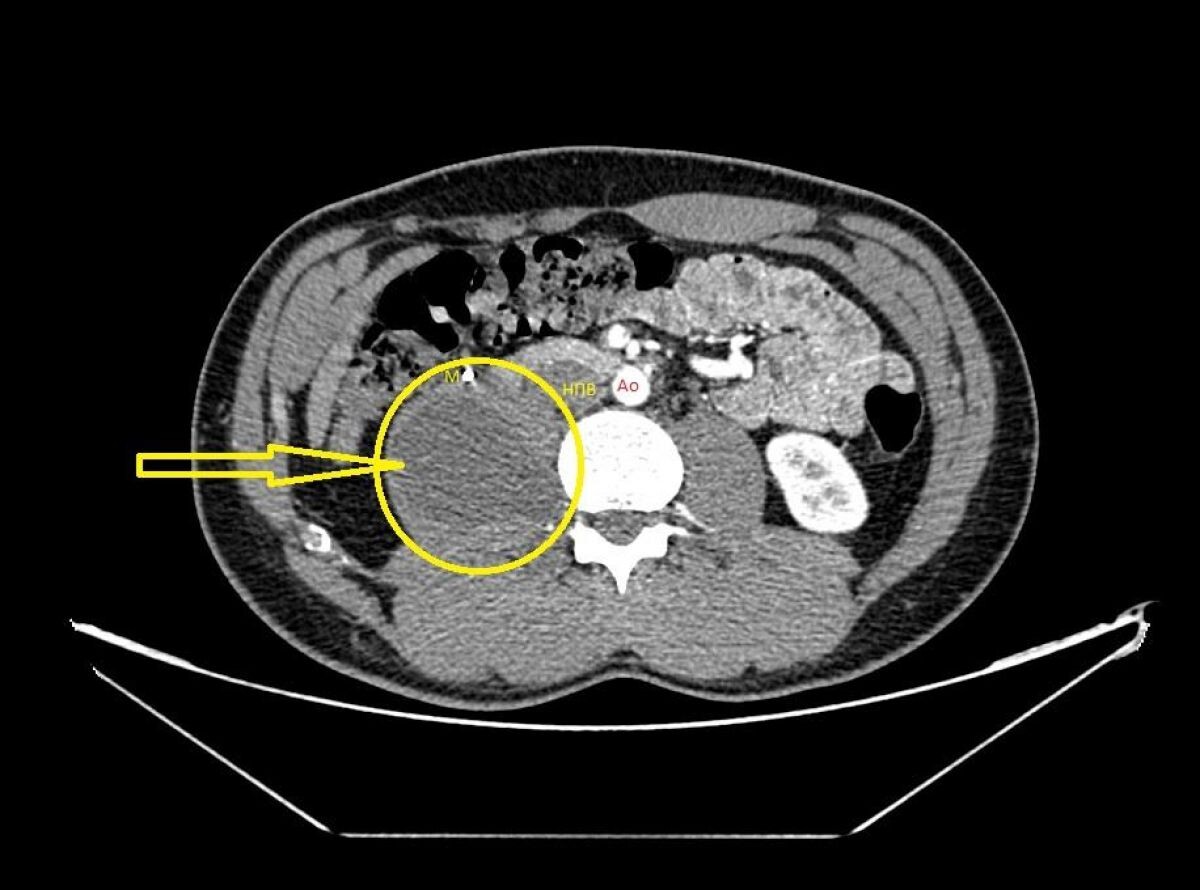

Медики провели оперативное лечение редкой опухоли забрюшинного пространства – гангионевромы вегетативной нервной системы. Молодой человек страдал от болей в правой поясничной области.

Сначала в Белгороде у него выявили камень мочеточника и опухоль брюшной полости за кишечником, за мочеточником, нижней полой веной. Она лежала на позвоночнике.